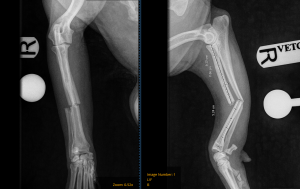

Radiographs showed she had sustained fractures to both of the bones in her foreleg—the radius and the ulna. This type of injury is quite painful and requires surgical stabilisation to heal properly and allow a return to normal function.

Pre-op X-rays